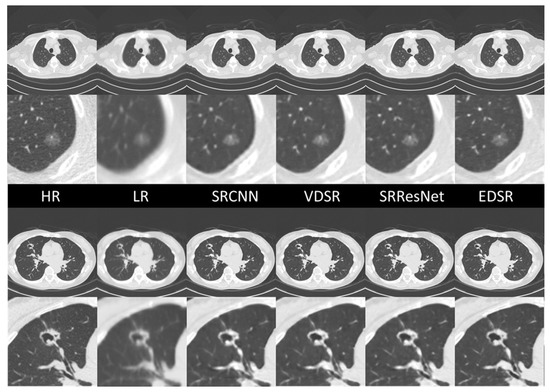

The ground-truth HR images, LR images, and sample comparisons for each SR DICOM slice generated along the sagittal axis are presented in Figure 9. The upper case is typical ground glass nodule that was confirmed to be early-stage lung cancer through surgical resection. All SR images maintain the ground glass features of this lesion, but only EDSR maintains the correct size and structure in terms of human visual quality. In the EDSR images, the fine structures of the surrounding lung markers are more clearly defined and correctly connected. The lower case is a cavitary lesion. Although the details of the upper border of the cavitary lesion are blurred in all SR images, the EDSR image preserves the arrangement of the proximal vessels and bronchi.

Figure 9. SR image samples of different AI models. All images were generated by applying SR models in the sagittal plan.